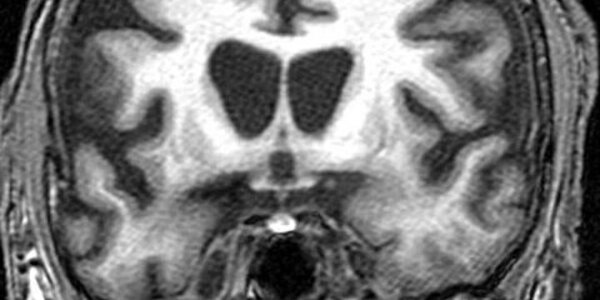

Childhood Abuse May Result In Structural Brain Changes

New research using magnetic resonance imaging (MRI) shows that abuse or emotional neglect during childhood combined with genetic factors can result in structural brain changes, rendering some individuals more vulnerable to  depression. The study results appear in Neuropsychopharmacology. 24 patients (aged 18-65 years) being treated as inpatients for major depression were investigated with high-resolution structural MRI and childhood stress assessments. Special analysis programs were used to measure brain regions. These patients were compared with 27 healthy control subjects from the…